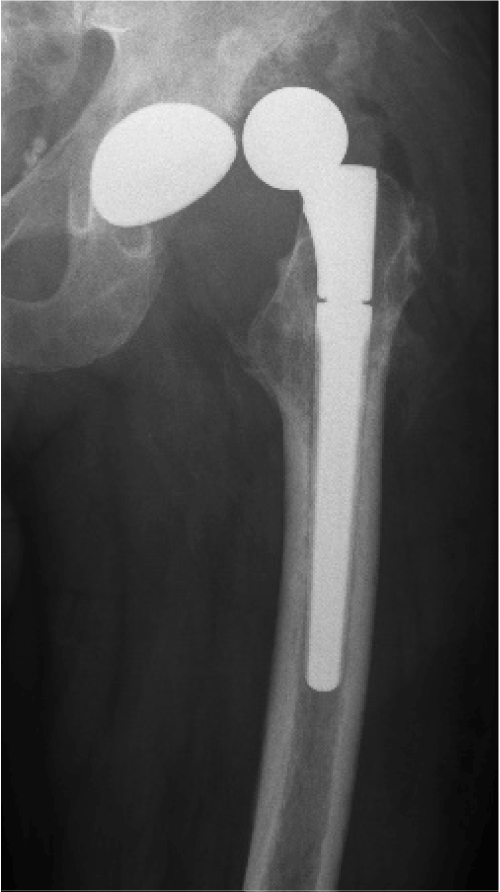

In August 2013 THA was performed due to a girdlestone situation after septic osteoarthritis of the hip (Figure 1) in a 46 year old male patient using a MRP Titan revision stem (Diameter: 18mm, length: 140 mm) (Peter Brehm GmbH, Weisendorf, Germany) and a cementless cup (Allofit - IT; Diameter 54 mm, Zimmer, Warsaw, USA) and a ceramic on ceramic bearing (head diameter: 36 mm) (Figure 2). The patient was 175 cm tall and weighed 105 kg (body mass index: 34.3 Kg/m2). 2 weeks later revision surgery due to recurrent dislocation (Figure 3) was performed. Revision of the acetabular component was done using an Allofit - Classic- cup, Diameter 56 mm (Zimmer, Warsaw, USA)). The neck component was exchanged from small to medium size (Figure 4). A ceramic on PE bearing was implanted (head diameter: 32 mm). Postoperative healing was uneventful. The patient was out of any complaints. In February 2016 the patient started suffering from slight thigh pain but detected crepitation in the region of the left hip. X-ray of the left hip in 2 planes in May 2016 revealed an asymmetrically gap of the stem / neck junction (Figure 5). During revision surgery of the left hip breakage of the cone of the morse taper junction was visible (Figure 6). Removal of the well-fixed stem was performed via a distal fenestration. After fixation with cerclage wires a bended MRP Titan revision stem (Diameter: 19 mm, Length: 200mm with long neck and extension sleeve) was implanted using a 32 mm ceramic head (Figure 7). Postoperative healing was uneventful.

Figure 7. X - ray of the left hip in 2 planes: ap view a. and lateral; b. view shows revision arthroplasty of the hip using a long bended MRP Titan revision stem with long neck and extension sleeve.